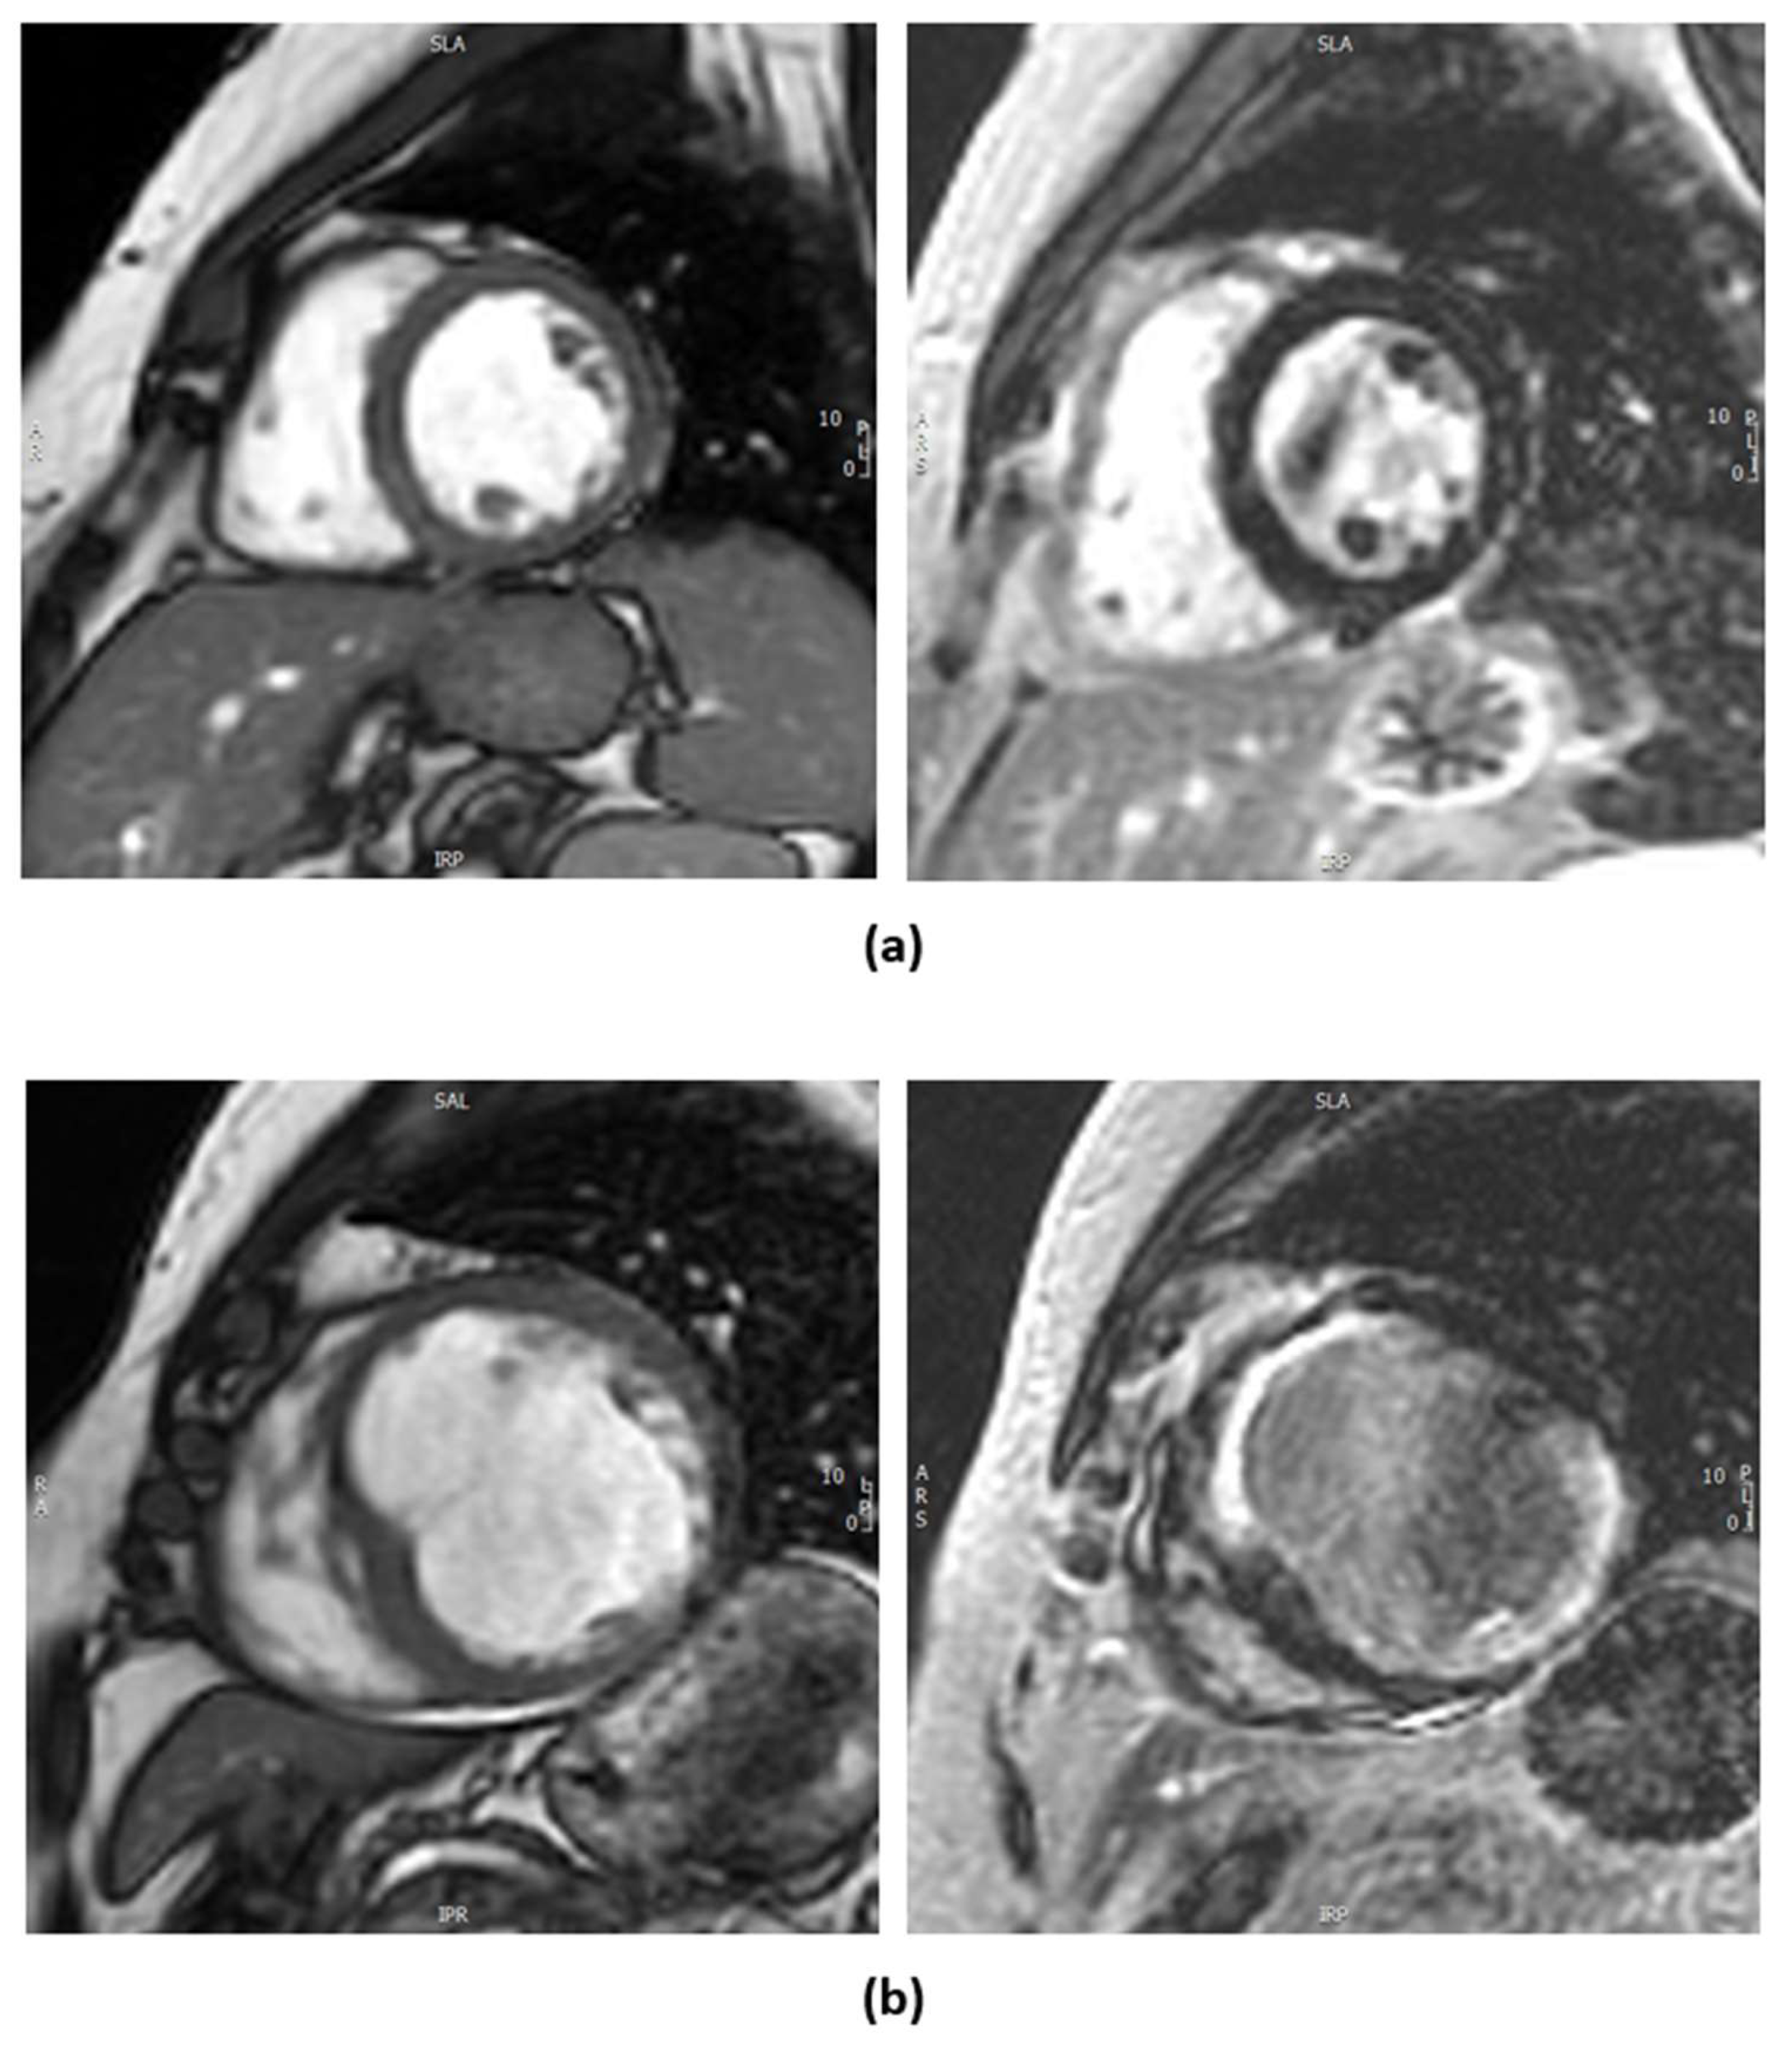

There are two methods of myocardial viability testing by CMRI. One involves dobutamine to assess for contractile reserve and the other is the evaluation of late gadolinium enhancement (LGE) looking into the volume of distribution of gadolinium-based contrast agents in the extracellular space, which is inversely related to the proportion of viable myocardial cells (Figure 2), with the latter as the more preferred and commonly used technique for assessing viability [21]. In a canine model, LGE-CMRI reliably differentiated between reversible and irreversible myocardial injury, with hyperenhancement corresponding to regions of necrosis or fibrosis and the absence of hyperenhancement indicating viable myocardium regardless of wall motion abnormalities [25]. Scar within the myocardium has significant prognostic implications as it implies irreversible injury and does not lead to reversible LV dysfunction; however, regionally thinned myocardium (defined as an end-diastolic wall thickness of ≤5.5 mm) [6], often misinterpreted as non-viable scar tissue, may recover in contractility and wall thickness after revascularization if the scar burden is limited (≤50% transmural extent of infarction) [26]. However, the availability and high cost of CMRI can be limiting factors, and its use requires significant expertise.

Figure 2.

Contrast cardiac MRI with gadolinium contrast. (a) Left image shows a 2D cine image clip of mid-ventricle short axis of a patient with ischemic cardiomyopathy. The image to the right corresponds to post-gadolinium contrast imaging showing no late gadolinium enhancement (LGE) indicating viable myocardium. (b) Left image shows a 2D cine image clip of mid-ventricle short axis of another patient. There is thinning of the anteroseptal, anterior, and inferolateral segments. The right image corresponds to post-gadolinium imaging with full-thickness LGE in the anterior, anteroseptal, and inferolateral segments indicating non-viable myocardium in the left anterior descending artery (LAD) and left circumflex (LCx) territories.